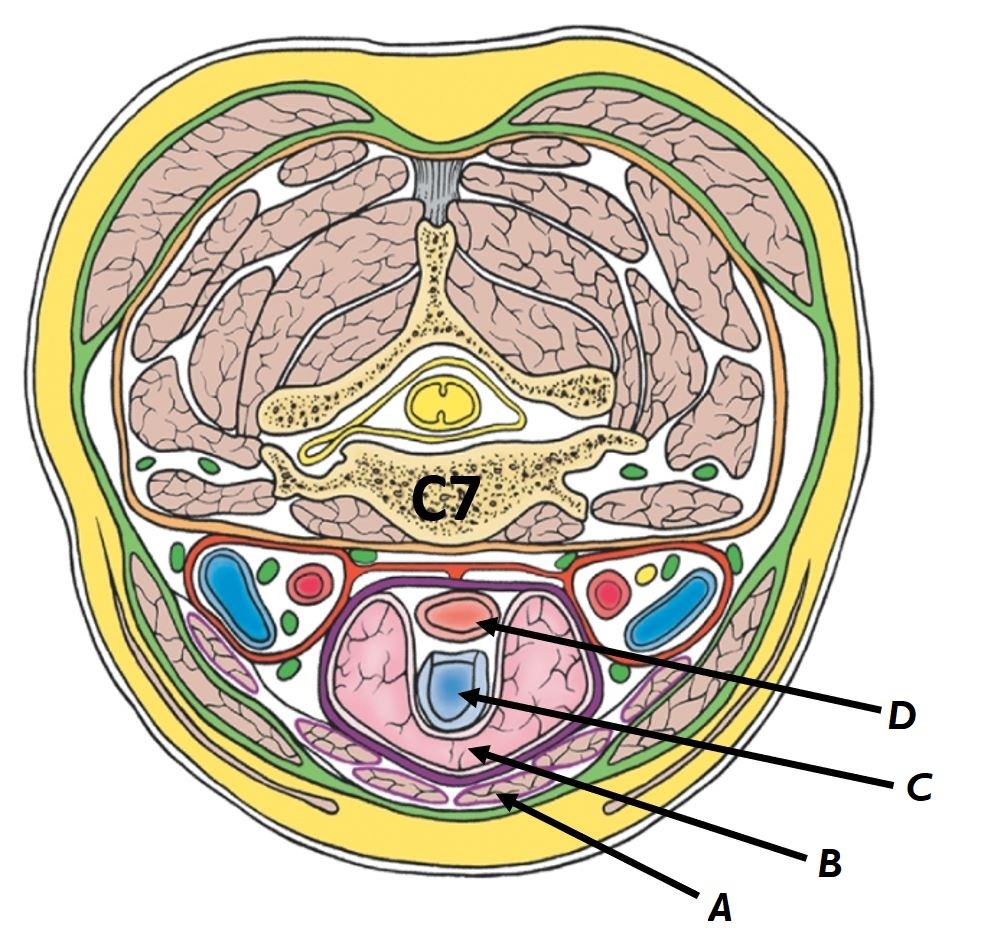

Name structures A to D

A - Pretracheal fascia

B - Carotid sheath

C - Prevertebral fascia

D - Investing fascia

Name structures A to D

A - Common carotid artery

B - Internal jugular vein

C - Vagus nerve

D - Deep cervical lymph nodes